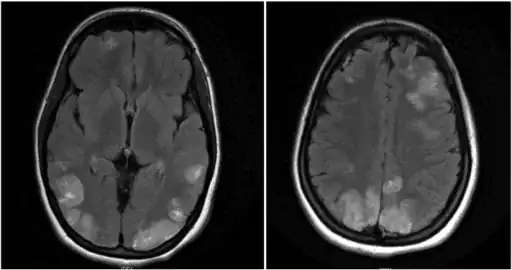

-

Image shows faint multifocal and bilateral hyperintensities in the frontal lobes and parietooccipital lobes, extending to the left greater than right posterior temporal regions -